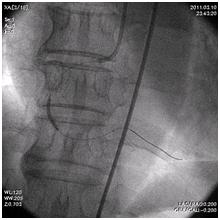

放射線部:愛媛県立南宇和病院